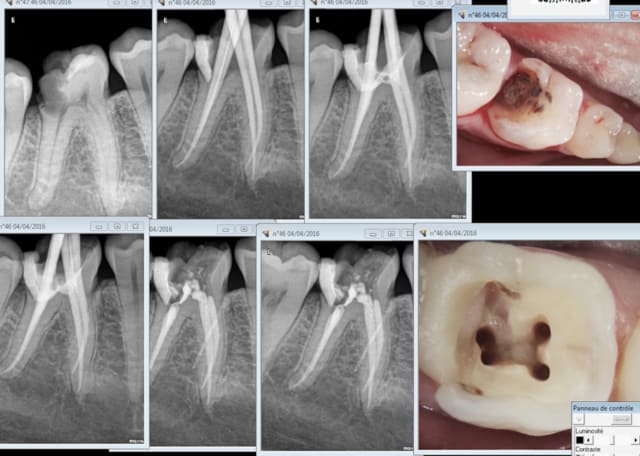

Tu peux nous mettre les quatre premières radios en grand pour que l'on voit un peu mieux.

une fusée de gutta aussi bien cylindrique ça me parait bizarre.

Combien de temps pour cette endo 4 canaux ?

Radio cone en place , cone scellé, cone condensé. Pas de bip intempestif au localisateur d'apex, je vois pas ou j'ai fait une connerie. Pour une fois ou je mets pas la digue ( urgence) . -)

45 mn mais j'ai ramé à l'anesthésie. . J'avais un trou de 30 mn et une consult derrière que j'ai prise sur mon 2 ième fauteuil. je pensais ouvrir et voir ca plus tard mais ca me faisait chier de refaire une anesthésie, j'en ai oublié la digue. mais pas la reconstitution pré endo. -) -)